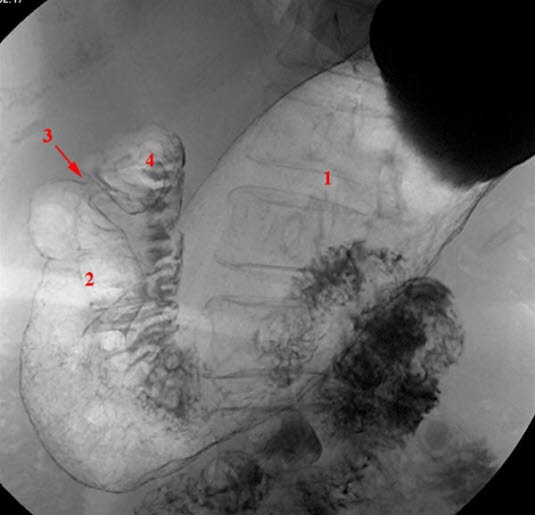

Fra spiserøret kommer maten over i magesekken (ventrikkelen) (se figur). En fylt magesekk rommer vanligvis ca. 1,5 liter. Den ligger øverst i midtre del av bukhulen og har en avlang og krummet fasong. Magesekken har en kort og en lang side, og den smalner av før den går over i tolvfingertarmen (duodenum). Saltsyre og stoffer som starter nedbrytingen av føden (eks. pepsin), lages i slimhinnen i magesekken. Slimhinnen er kledd med et beskyttende slimlag som hindrer saltsyren i å etse hull på magesekken. Den nedsvelgde maten eltes ved at magesekken trekker seg sammen og utvider seg (såkalt peristaltisk aktivitet). Tolvfingertarmen har en C-form og er ca. 25 cm lang. Gallegangen og utførselsgangen til bukspyttkjertelen tømmer seg i tolvfingertarmen. Både galle og bukspytt er nødvendig for nedbrytningen av føden i tarmen.

Et magesår oppstår enten i magesekken eller i tolvfingertarmen (se figur). Sår i tolvfingertarmen forekommer ca. 5 ganger så hyppig som sår i magesekken.

Undersøkelsen fremstiller form, posisjon, slimhinnefolder, sammentrekninger og bevegelser av magesekken og øvre del av fordøyelseskanalen (se røntgenbildene over). Undersøkelsen omfatter vanligvis både øsofagus (spiserør = Ø), ventrikkel (V), duodenum (D) og øvre del av tynntarmen. På fagspråket brukes ofte betegnelsen røntgen Ø+V+D. Undersøkelsen foregår med bruk av kontrast og som regel med såkalt dobbelkontrast-metode, det vil si både kontrastvæske og luft. Røntgen av øvre del av magetarm-kanalen gjøres sjeldnere i dag enn før. Gastroskopi er en mer presis undersøkelse og gir anledning til direkte prøvetaking til mikrobiologiske undersøkelser og mikroskopi av vevsprøver (histologi).

Røntgenlegen ser etter uregelmessige relieff eller konturer i magesekkens vegg. Tiden det tar å tømme magesekken for kontrast, er også en viktig observasjon. Forsinket tømning kan være uttrykk for sykdom. Blant de hyppigste sykdommer som kan påvises, er magesår enten i magesekken eller tolvfingertarmen. Ofte kan det finnes arrforandringer i tolvfingertarmen etter tidligere magesår. Polypper og kreft i magesekken kan påvises med røntgen. Videre utredning gjøres som regel med gastroskopi, ultralyd, CT eller MR.